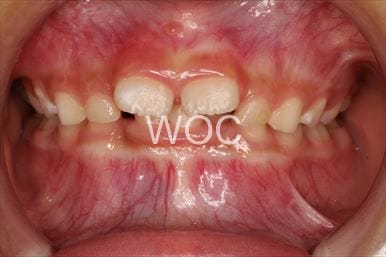

開咬

-

治療前1

-

治療前2

-

- 年齢:5歳4ヶ月

- 主訴:前歯で噛めない、おしゃぶりがやめられない

- 診断名:開咬

- 装置:機能的矯正装置

- 期間:5年2ヶ月 ※

- 費用:基本矯正料金:370,000円